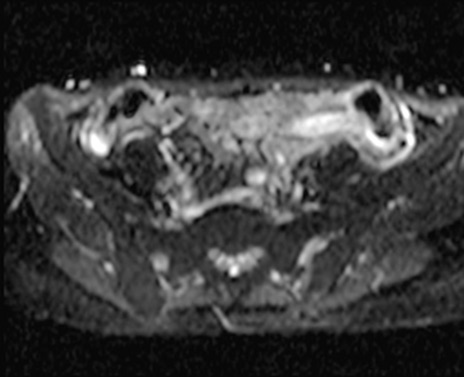

MRI(4日後)